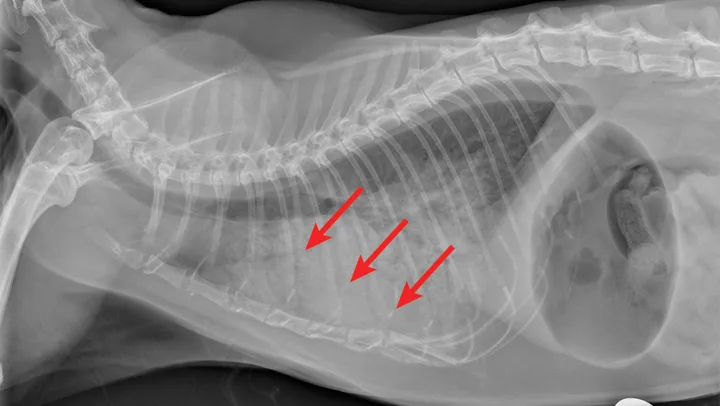

Overt cardiomegaly may be understated on radiographs because of changes in internal diameter that do not affect the overall cardiac silhouette. Vertebral heart score >9.3 supports a CHF diagnosis.1 Pulmonary venous congestion can be absent, and pulmonary arterial distension may be appreciated. The presence of pleural effusion with simultaneous pulmonary infiltrates is supportive of CHF (Figure 1).2

Congestive heart failure. Note the pleural effusion (arrows).